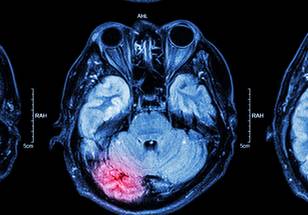

The HBOT protocol included 60 two-hour sessions in a hyperbaric chamber. During each session, participants alternated between breathing pure oxygen at twice the normal atmospheric pressure and regular air, cycling every 20 minutes. This alternation was designed to stimulate tissue healing by creating fluctuations in oxygen levels. Functional MRI imaging revealed improved connectivity in brain networks among HBOT participants, accompanied by significant reductions in PTSD symptoms. In contrast, no changes were observed in the placebo group, either clinically or in brain imaging.